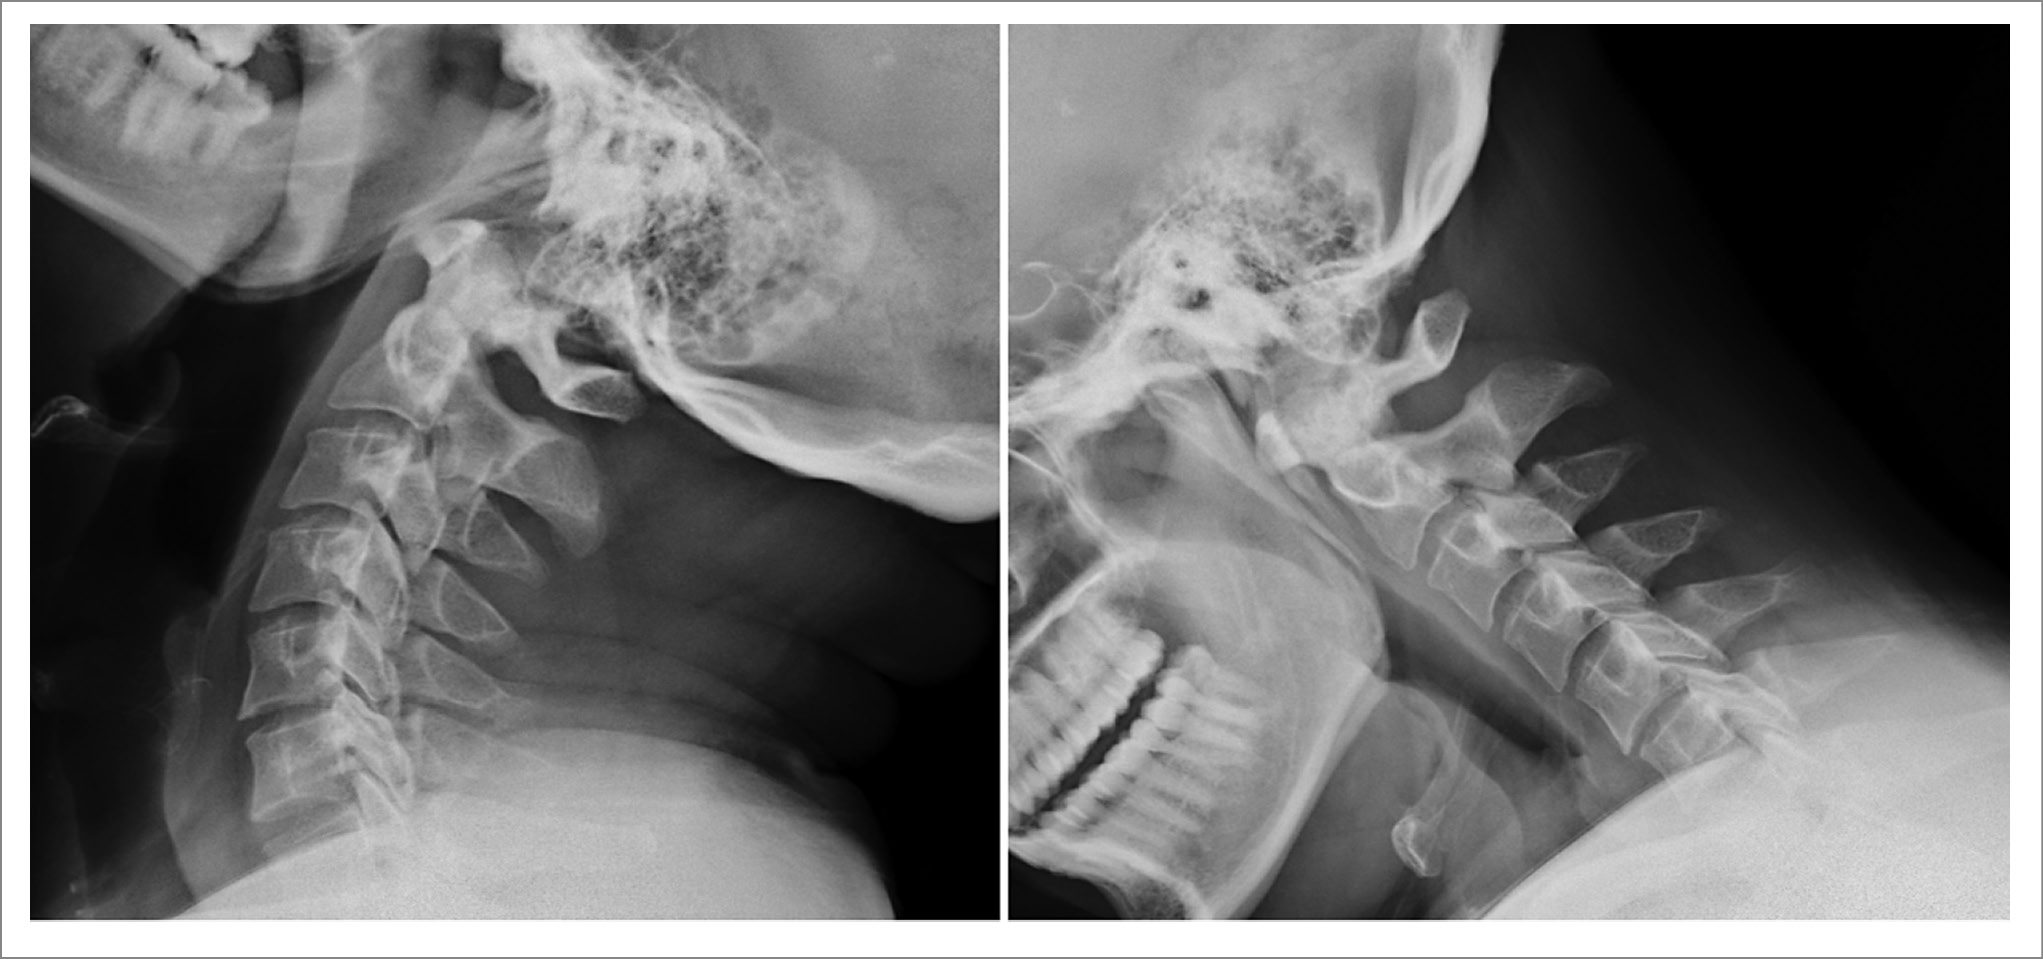

Проведена рентгенография ШОП с функциональными пробами: при функциональных пробах патологического смещения тел позвонков не выявлено. Рентгенологическая картина дегенеративных изменений ШОП показана на рис. 2.

Рис. 2. Рентгенография ШОП с функциональными пробами. Отсутствие патологического смещения тел позвонков.

Рентгенографию ШОП не используют для диагностики ЦР [22]. В нашем случае наблюдалось практически полное совпадение клинической симптоматики и нейровизализационной МРТ-картины. Учитывая признаки гипермобильности по данным нейроортопедического обследования, перед проведением мануальной терапии для исключения спондилолистеза и нестабильности ШОП выполнена функциональная рентгенография.